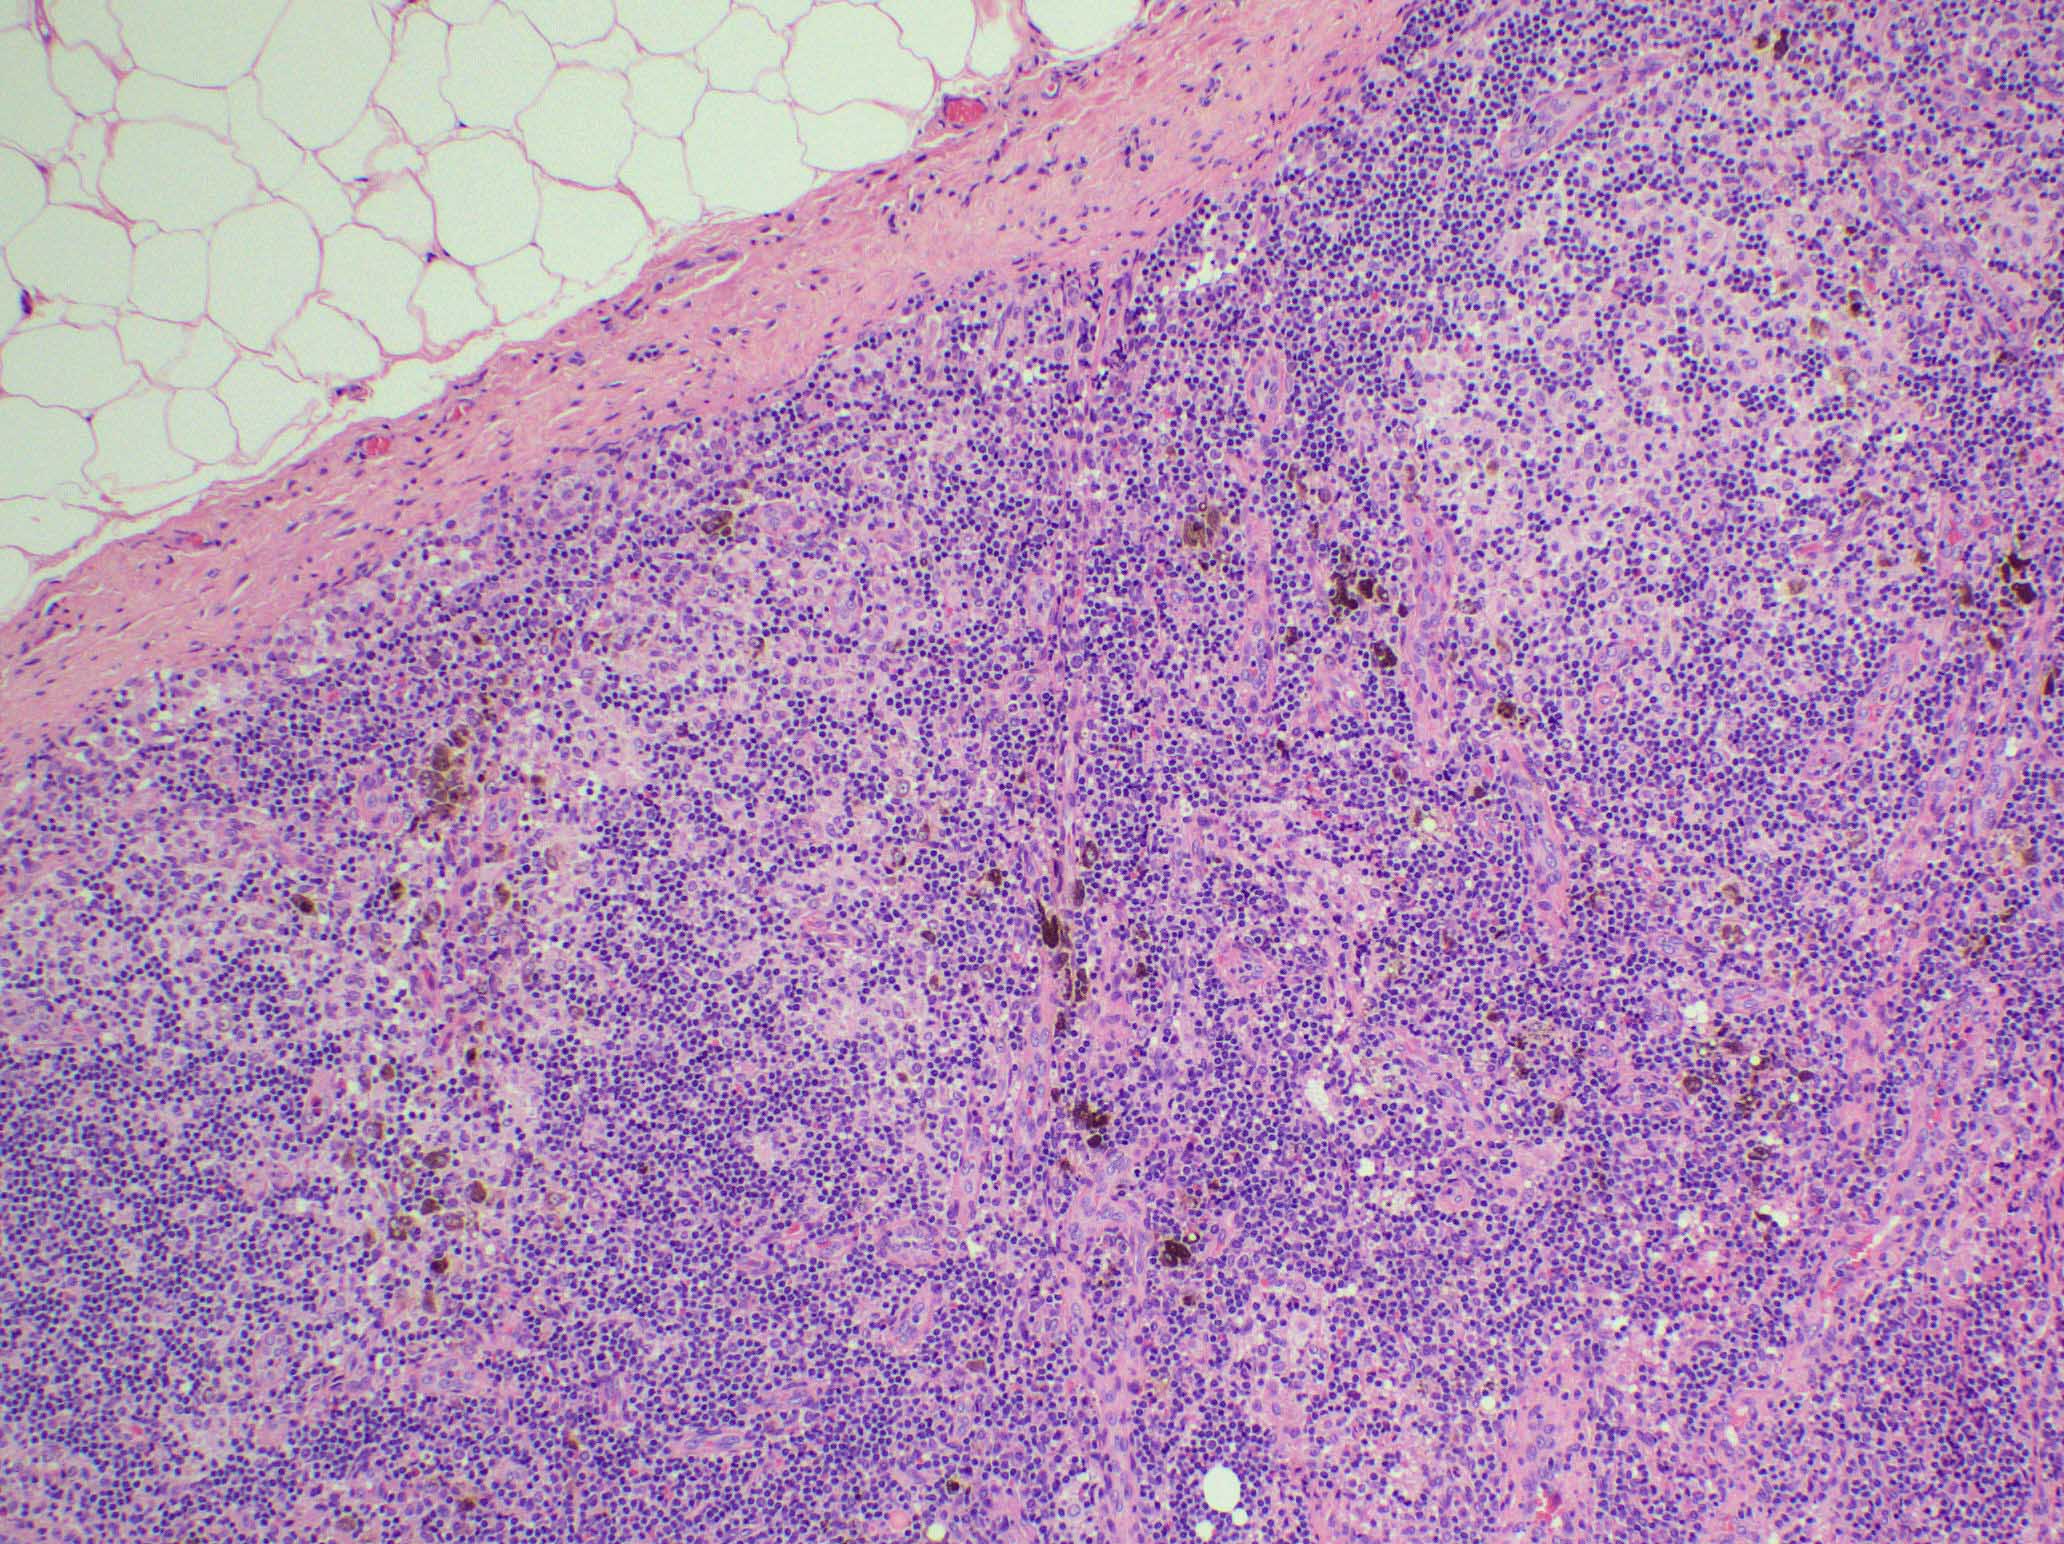

Microscopic (histologic) images

Contributed by Ingrid Tam, M.D., M.Sc., Emina Emilia Torlakovic, M.D., Ph.D. and Nikhil Sangle, M.D. (Case #396)

- Spectrum of changes from mild to severe, characterized by paracortical expansion with pale, irregularly shaped areas containing numerous pale staining histiocytes, interdigitating dendritic cells, Langerhans cells and occasional immunoblasts

- Predominance of interdigitating dendritic cells over Langerhans cells, which are indistinguishable on morphology alone

- Both cell types show ill defined cell borders with fine irregular reniform nuclear contours and occasional nuclear grooves

- Paracortical or sinusoidal histiocytes and macrophages often contain cytoplasmic melanin pigment but they also can contain hemosiderin or lipid

- Medullary plasmacytosis is variable

- Distended sinuses with histiocytes, plasma cells and eosinophils can be present

- Variable, usually mild capillary hyperplasia